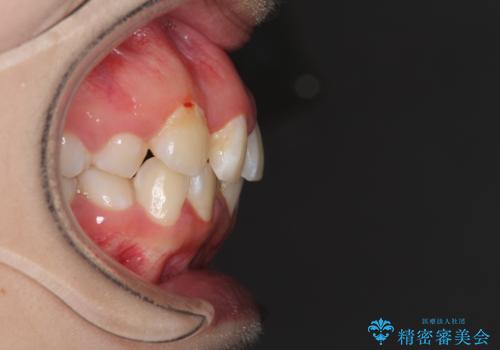

- 骨格的な咬み合わせのズレ、前歯のデコボコとクロスバイトを気にして来院された患者様です。

口元の突出感が若干あり口が閉じにくく、デコボコが強いため、上下左右の小臼歯計4歯を抜歯し、ワイヤー装置による矯正治療を行うこととしました。